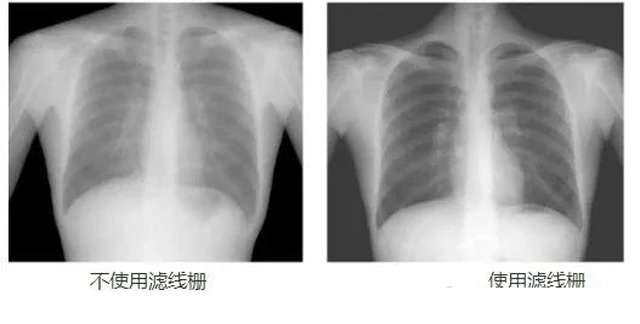

DR影像X射線在醫學檢查成像有著廣泛的使用。但是它的散射線影響成像質量問題。濾線柵的發明使用很好的解決了這個問題,構造簡單鉛條粗,密度和柵比規格單一,能減散射線但吸收較多原發射線。伴隨這醫療影像設備技術的發展,這個濾線柵的工藝製造技術有改進,鉛條變薄,柵密度和柵比有更多的選擇。特別是材料方麵有新組合,填充物也依不同成像要求優化。特別是移動DR這類型的DR設備的出現,濾線柵也設計成立方便拆卸形的,方便使用。被照體情況決定是否使用,更好平衡成像質量與射線劑量。

焦距(f):斷麵看鉛條延長線會聚點到柵板垂直距離,即柵板焦距(半徑)。柵密度(N):每厘米範圍內含有的鉛條數,一般40~65線/cm。柵比(R):鉛條高度與柵條間隙之比,比值越高濾除散射線能力越強,一般8:1~14:1之間。結構組成:3~5mm薄板,用0.05~0.1mm鉛條,夾持在鋁或紙之間平行或按斜率排列,相鄰鉛條間用易透X線物質填充定位、黏合,如木、紙、鋁片等。

放置方麵:置於人體與片盒間,聚焦麵朝向X線入射方向,X線焦點放鉛條會聚線上,不能反置,X線中心對準濾線柵中心,左右偏移不超3cm,傾斜X線管要與鉛條排列方向平行。攝影時焦距改變不超焦距的25%;活動式濾線器運動時間至少長於曝光時間的1/5;因吸收原發射線要適當增加曝光條件;四肢薄位置一般不用濾線柵;不同千伏對應不同柵比;立位胸片架、乳腺DR攝影等有各自特定濾線柵要求。